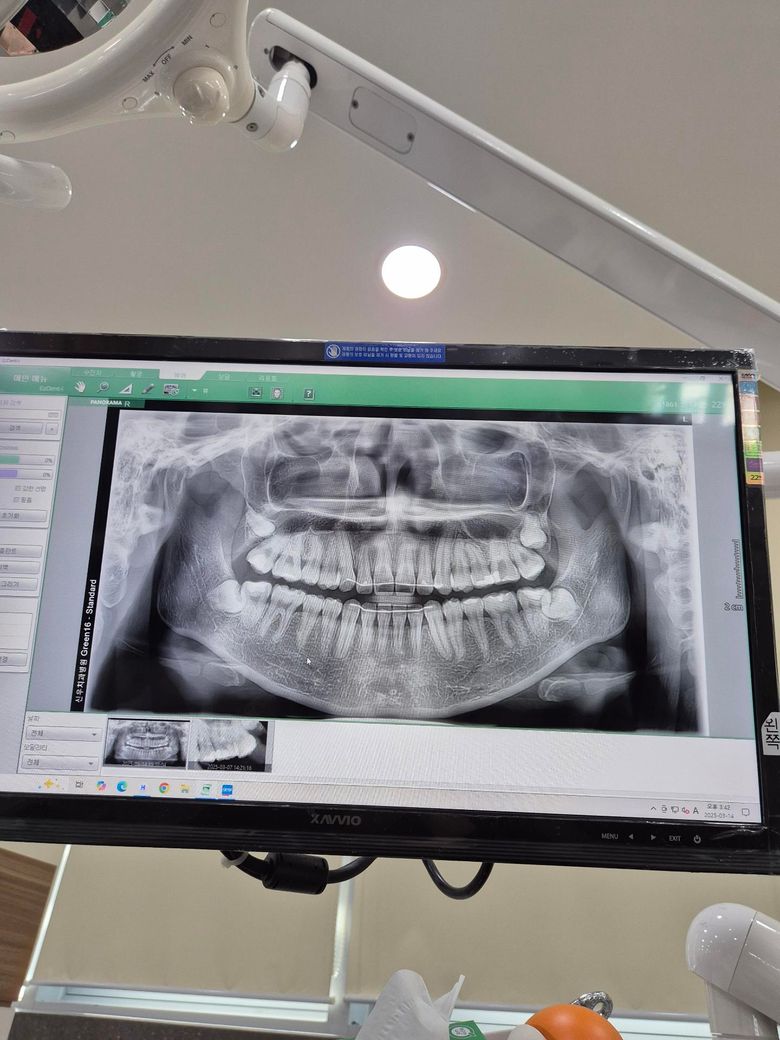

x레이 사진은 5개월 전 사진입니다. 나중에 치아가 흔들리까봐 걱정됩니다.

• 2번 째 사진

사진으로 봤을 경우에는 잇몸 퇴축이 조금 진행된 것으로 보입니다. 잇몸 대축은 잇몸에 너무 강한 자극이 가해지면서 생기기 때문에 양치질을 할 때 잇몸에 넘어가는 자극이 가해지지 않다고 하는 것이 좋습니다.

나이 대비하여 잇몸이 조금 퇴축된 것은 맞습니다. 지금부터 관리를 더 잘해주셔야겠습니다.

송곳니는 원래 잇몸퇴축이 다른 치아보다 먼저, 더 많이 이뤄집니다 교정 후 잇몸퇴축이 동반되는 것은 흔한 부작용 중 하나이고요 앞으로 잇몸관리 꾸준히 치과에서 받으세요